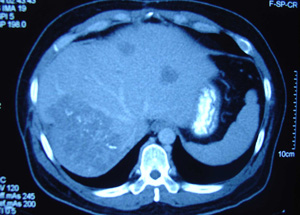

CT Scan Report: 3 October 2008: There is ill-defined hypodense lesion at Segment VI. It measures 3.5 x 3.5 cm. Feature is suggestive of right lobe hepatoma.

A CT scan done of 10 February 2009 indicated:

- Worsening of the liver with increase in the number and size of the liver nodules.

- There was thrombosis of the adjacent portal vein extending partially to the main portal vein.